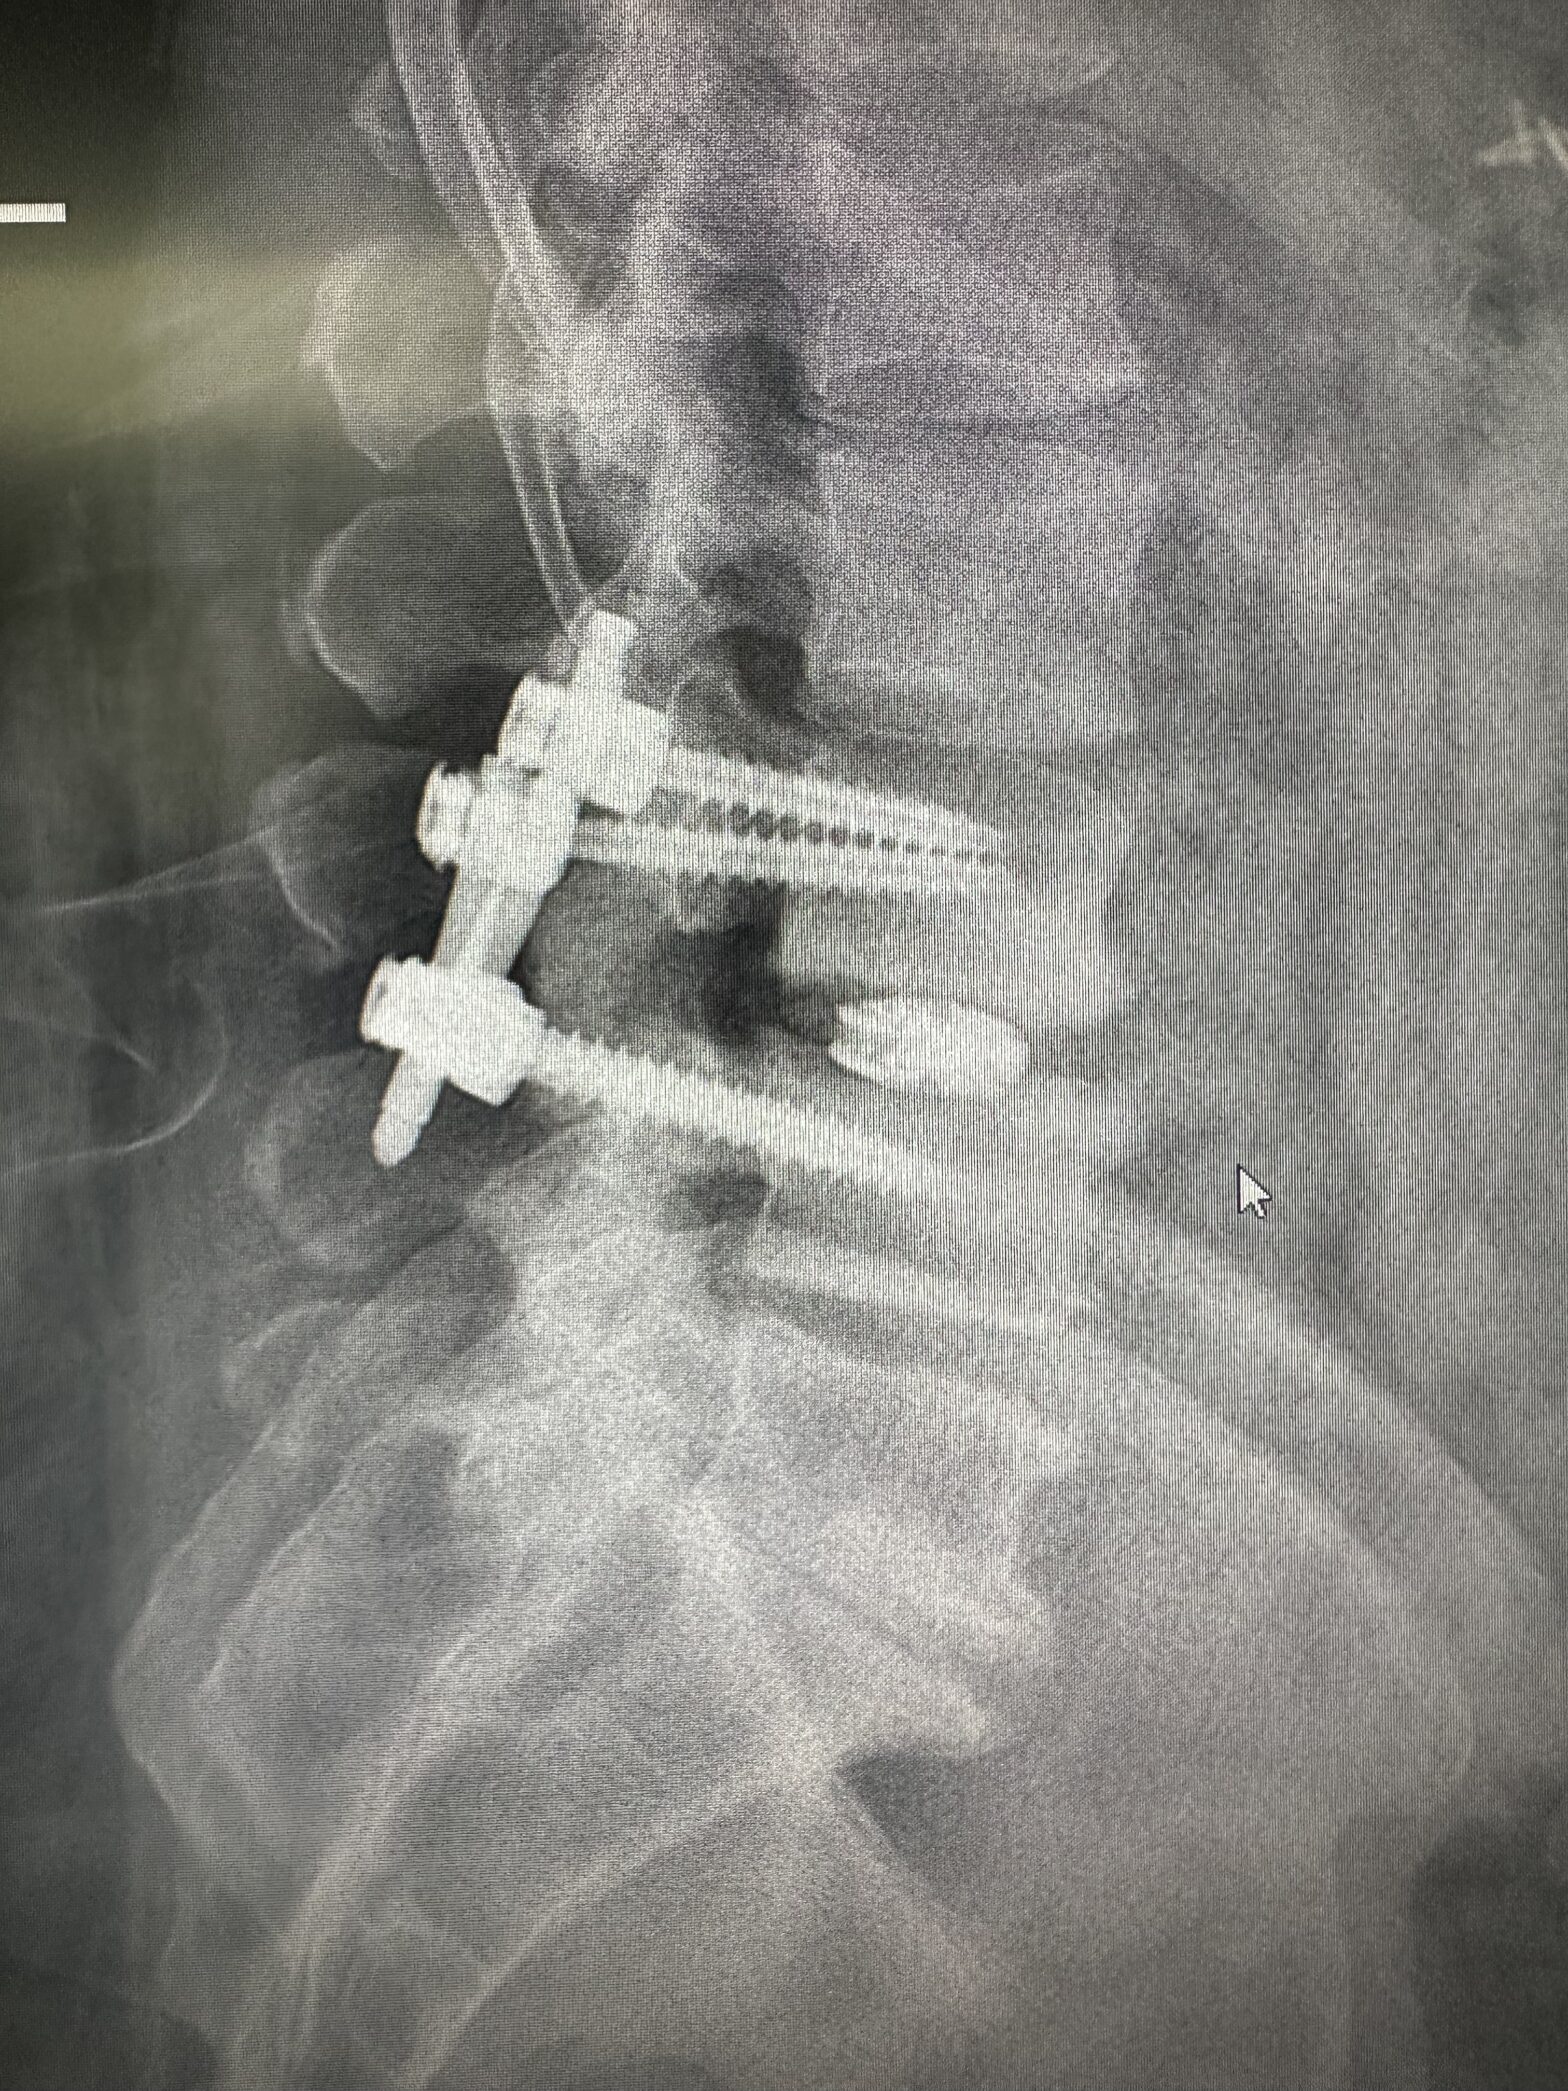

Minimally Invasive Spinal Fusion

Stabilization of the spine using small incisions and specialized surgical instruments.